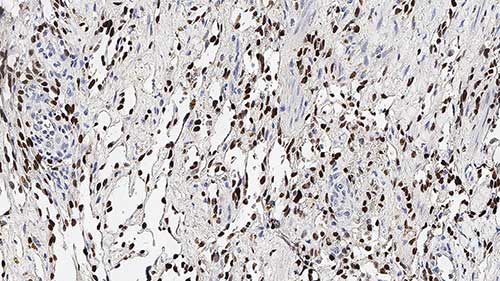

Human prostatic adenocarcinoma: immunohistochemical staining for AMACR. Note the characteristic granular cytoplasmic staining of malignant cells. AMACR: clone EPMU1

Alpha-methylacyl-CoA racemase (AMACR), also known as p504s, is a mitochondrial and peroxisomal enzyme that is involved in bile acid biosynthesis and beta-oxidation of branched-chain fatty acids. AMACR is essential in lipid metabolism, and is expressed in normal liver (hepatocytes), kidney (tubular epithelial cells) and gall bladder (epithelial cells). Expression has also been found in lung (bronchial epithelial cells) and colon (colonic surface epithelium). Expression is granular and cytoplasmic. AMACR expression can also be found in hepatocellular carcinoma and kidney carcinoma. Past studies have also shown that AMACR is expressed in various colon carcinomas (well, moderately and poorly differentiated) and over expressed in prostate carcinoma.